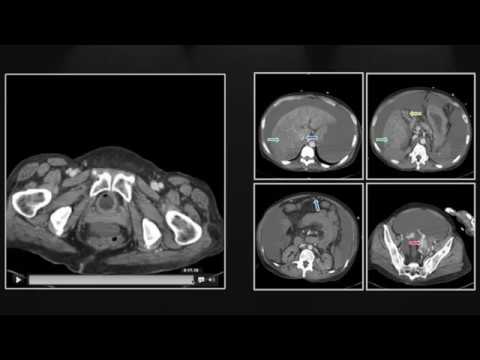

Another key technique is CT Scans, or computed tomography scans. They provide detailed cross-sectional images of your organs, kind of like slicing a loaf of bread to see what’s inside each slice! With cirrhosis, CT scans can reveal changes in liver texture and size that might indicate scarring. They also help spot potential complications, like tumors or fluid buildup.

CT scans, or computed tomography scans, are like fancy X-rays that take detailed pictures of your insides. They help doctors look at your liver structure and detect any abnormalities. Here are some important points about their accuracy:

• High Sensitivity: Studies show that CT scans have a high sensitivity for detecting significant fibrosis and cirrhosis. This means they can often pick up on major issues quite reliably.

• Specificity Issues: While they are good at spotting problems, CT scans can sometimes be less specific. This means they might indicate cirrhosis when there isn’t any or miss it altogether in some cases.

• Contrast Agents: Using contrast agents—substances that enhance the images—can improve accuracy significantly. They help differentiate between normal and scarred tissue more effectively.

• Combination with Other Tests: It’s not just about the CT scan alone! Doctors often pair it with blood tests and ultrasounds for a clearer picture of what’s happening in a patient’s liver.

The bottom line? While CT scans are invaluable in diagnosing liver cirrhosis due to their high sensitivity, they’re not without their pitfalls. It’s crucial for doctors to consider multiple types of imaging along with patient history and symptoms when determining the best approach for diagnosing this condition.